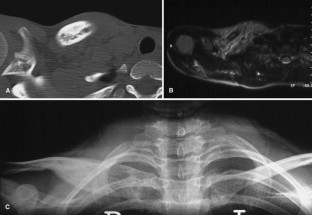

Fig. 1.